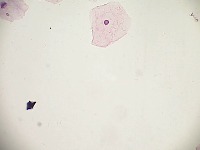

Cervical Cancer Screenings: The "PapDetector" can be used for the initial screening in detecting cervical cancer. Its ability to classify different cellular structures could provide invaluable assistance in large-scale cervical cancer screening tests, making the entire process more efficient.

Medical Research: Scientists and researchers can use this model to identify and further study these cellular structures. This could improve the understanding of various conditions related to cell abnormalities, thus leading to new treatments or diagnostic methods.

Training Medical Students: The "PapDetector" can also serve as a learning tool for medical students, enabling them to visually learn and identify cell structures that denote normal and abnormal cases.

Pharmaceutical Development: The computer vision model could be utilized in the pharmaceutical industry to screen the effects of drug treatments on cell morphology – highlighting normal, HSIL, LSIL, ANORMAL, Koilocytes changes in response to pharmaceutical compounds. This information would be useful in drug development and efficacy trials.